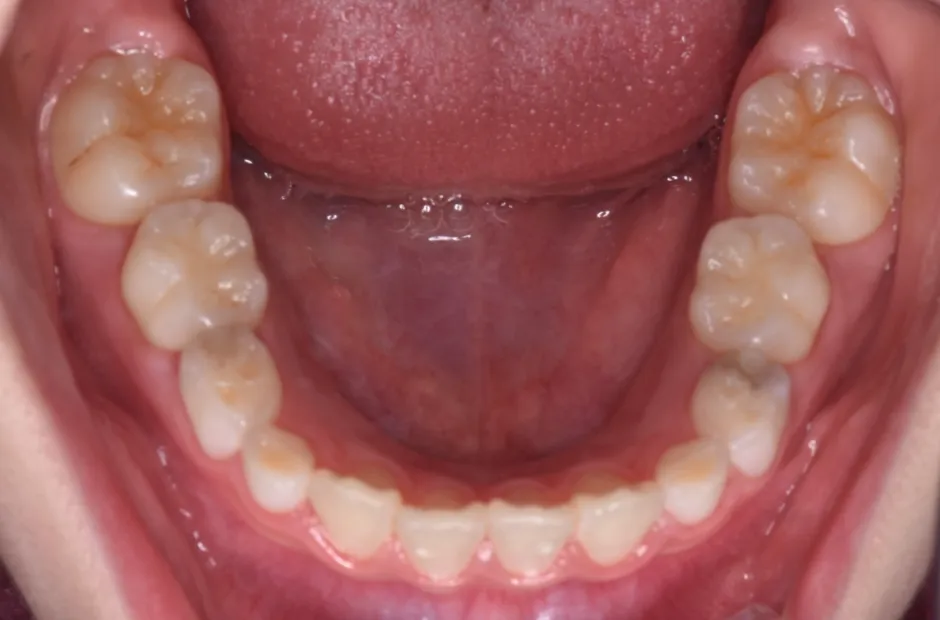

拡大床装置

叢生

| 診断名・主訴 | 叢生 |

|---|---|

| 年齢・性別 | 10歳・女性 |

| 治療期間・回数 | 2年半 |

| 治療に用いた主な装置 | 拡大床装置 |

| 抜歯部位 | なし |

| 治療費 | 30万円(税抜) |

| リスク・副作用 | 装置による違和感・疼痛・歯肉退縮・歯根吸収・虫歯のリスクなど |

治療前

治療中

治療後